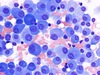

Immune Thrombocytopenic Purpura

| (increased numbers of megakaryocytes)

Follicular Lymphoma

(aggregates of packed follicles [arrows])